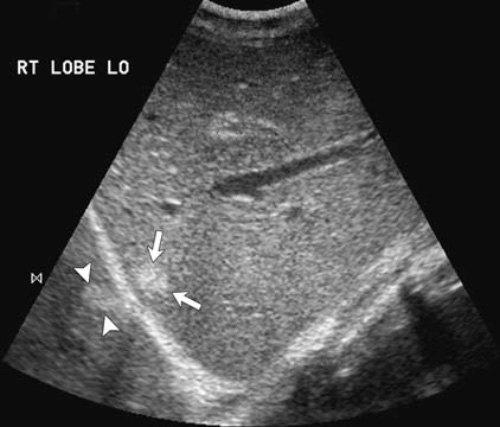

Возникновение артефакта зеркального изображение обусловлено наличием сильных отражателей. В этом случае волны отражаются от косо ориентированного зеркального отражателя, после чего звук отражается уже от вторичного объекта, достигая датчика в виде косо ориентированного изображения сильного отражателя. Поскольку цифровая обработка не включает алгоритм обработки внутреннего отражения, на изображении отображается положение эха на основании пропорциональной зависимости между временем, за которое звуковая волна преодолевает конкретное расстояние, и глубину, из которой возвращается эхо. Таким образом, глубоко расположенные сильные отражатели образуют зеркальное изображение. Артефакт зеркального отражения часто вызывает диафрагма (сильный отражатель), например, разного рода поражения печени могут отражаться диафрагмой, тем самым создавать ложное впечатление поражения легких (рисунок 4).

Рисунок 4. УЗИ печени: артефакт зеркального отражения. Стрелками указана гемангиома печени, которая отражается диафрагмой. Отражение находится позади диафрагмы, в результате чего отображается второе ложное повреждение (обозначено указателями), хотя на самом деле в этой зоне уже находится легкое